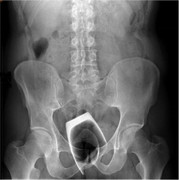

Khó ăn uống, buồn nôn, cụ bà đi khám được các bác sĩ chẩn đoán u đại trực tràng trái, lồng đại tràng sigma - trực tràng, gây tắc ruột cần phải phẫu thuật.